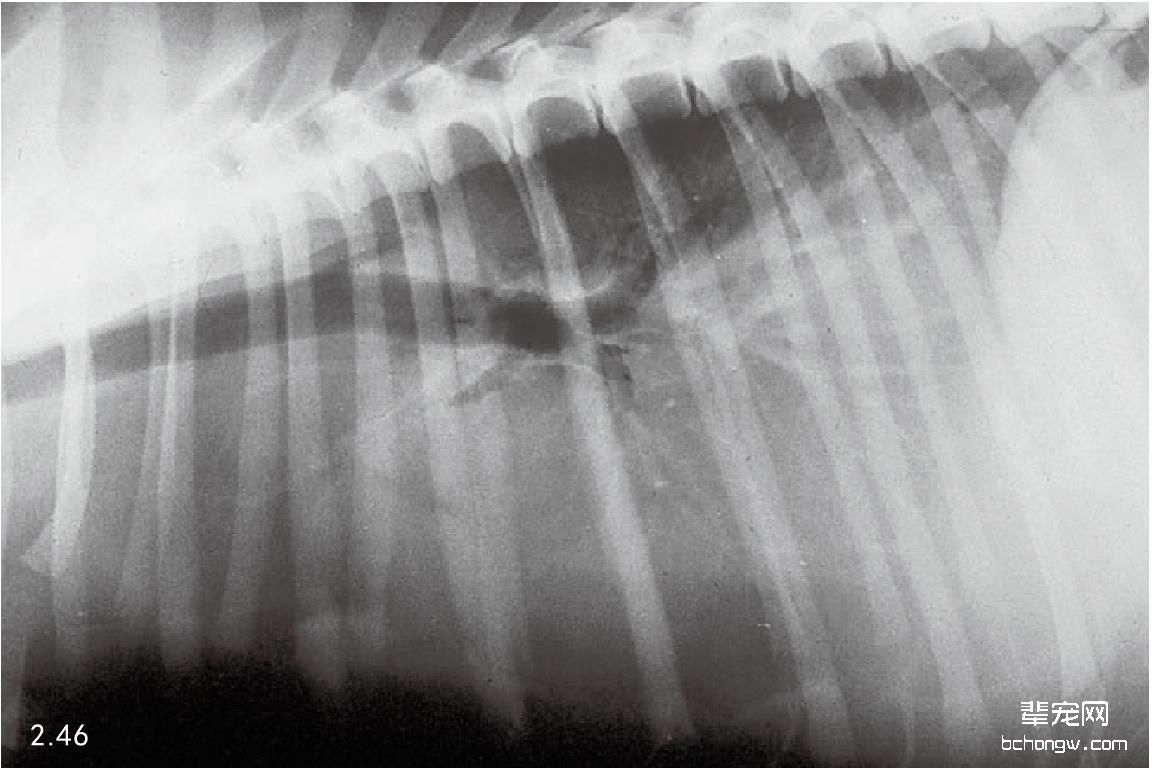

X线检查 侧面影像中,前部胸腔纵隔肿块引起气管偏离,心脏后侧移位和前侧心脏边缘消失;在背腹侧影 像中前部纵隔增宽和肺前叶后侧移位(图2.44和图2.45)。胸腔壁肿瘤通常引起软组织膨胀,导致邻近的肋骨移 位,作为额外的胸膜肿块延伸进入胸腔(图2.46和图2.47)。

图2.46 患有胸腔壁肿瘤的一只2岁牧羊犬的侧面胸腔X线片。